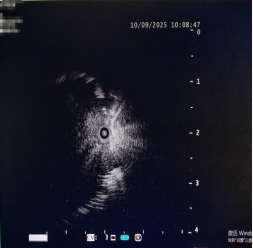

径向超声小探头(rp-EBUS)如同为支气管镜装上了“透视眼”。当细支气管镜接近目标区域时,微型超声探头被推出,通过管壁对周围肺组织进行360度扫描,精确定位支气管腔外结节的准确位置和边界,如同照亮了黑暗中的目标。